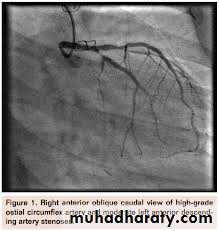

D-Cardiac catheterization :(normal coronary arteries ) to exclude coronary artery disease

$Cardiac catheterization

*Surgery :Outflow tract obstruction can be improved by partial surgical resection (myectomy) to improve symptoms in symptomatic patient who not responsive to medical therapy*By Catheterization : iatrogenic infarction of the basal septum (alcoholic septal ablation) using a catheter-delivered alcohol solution.